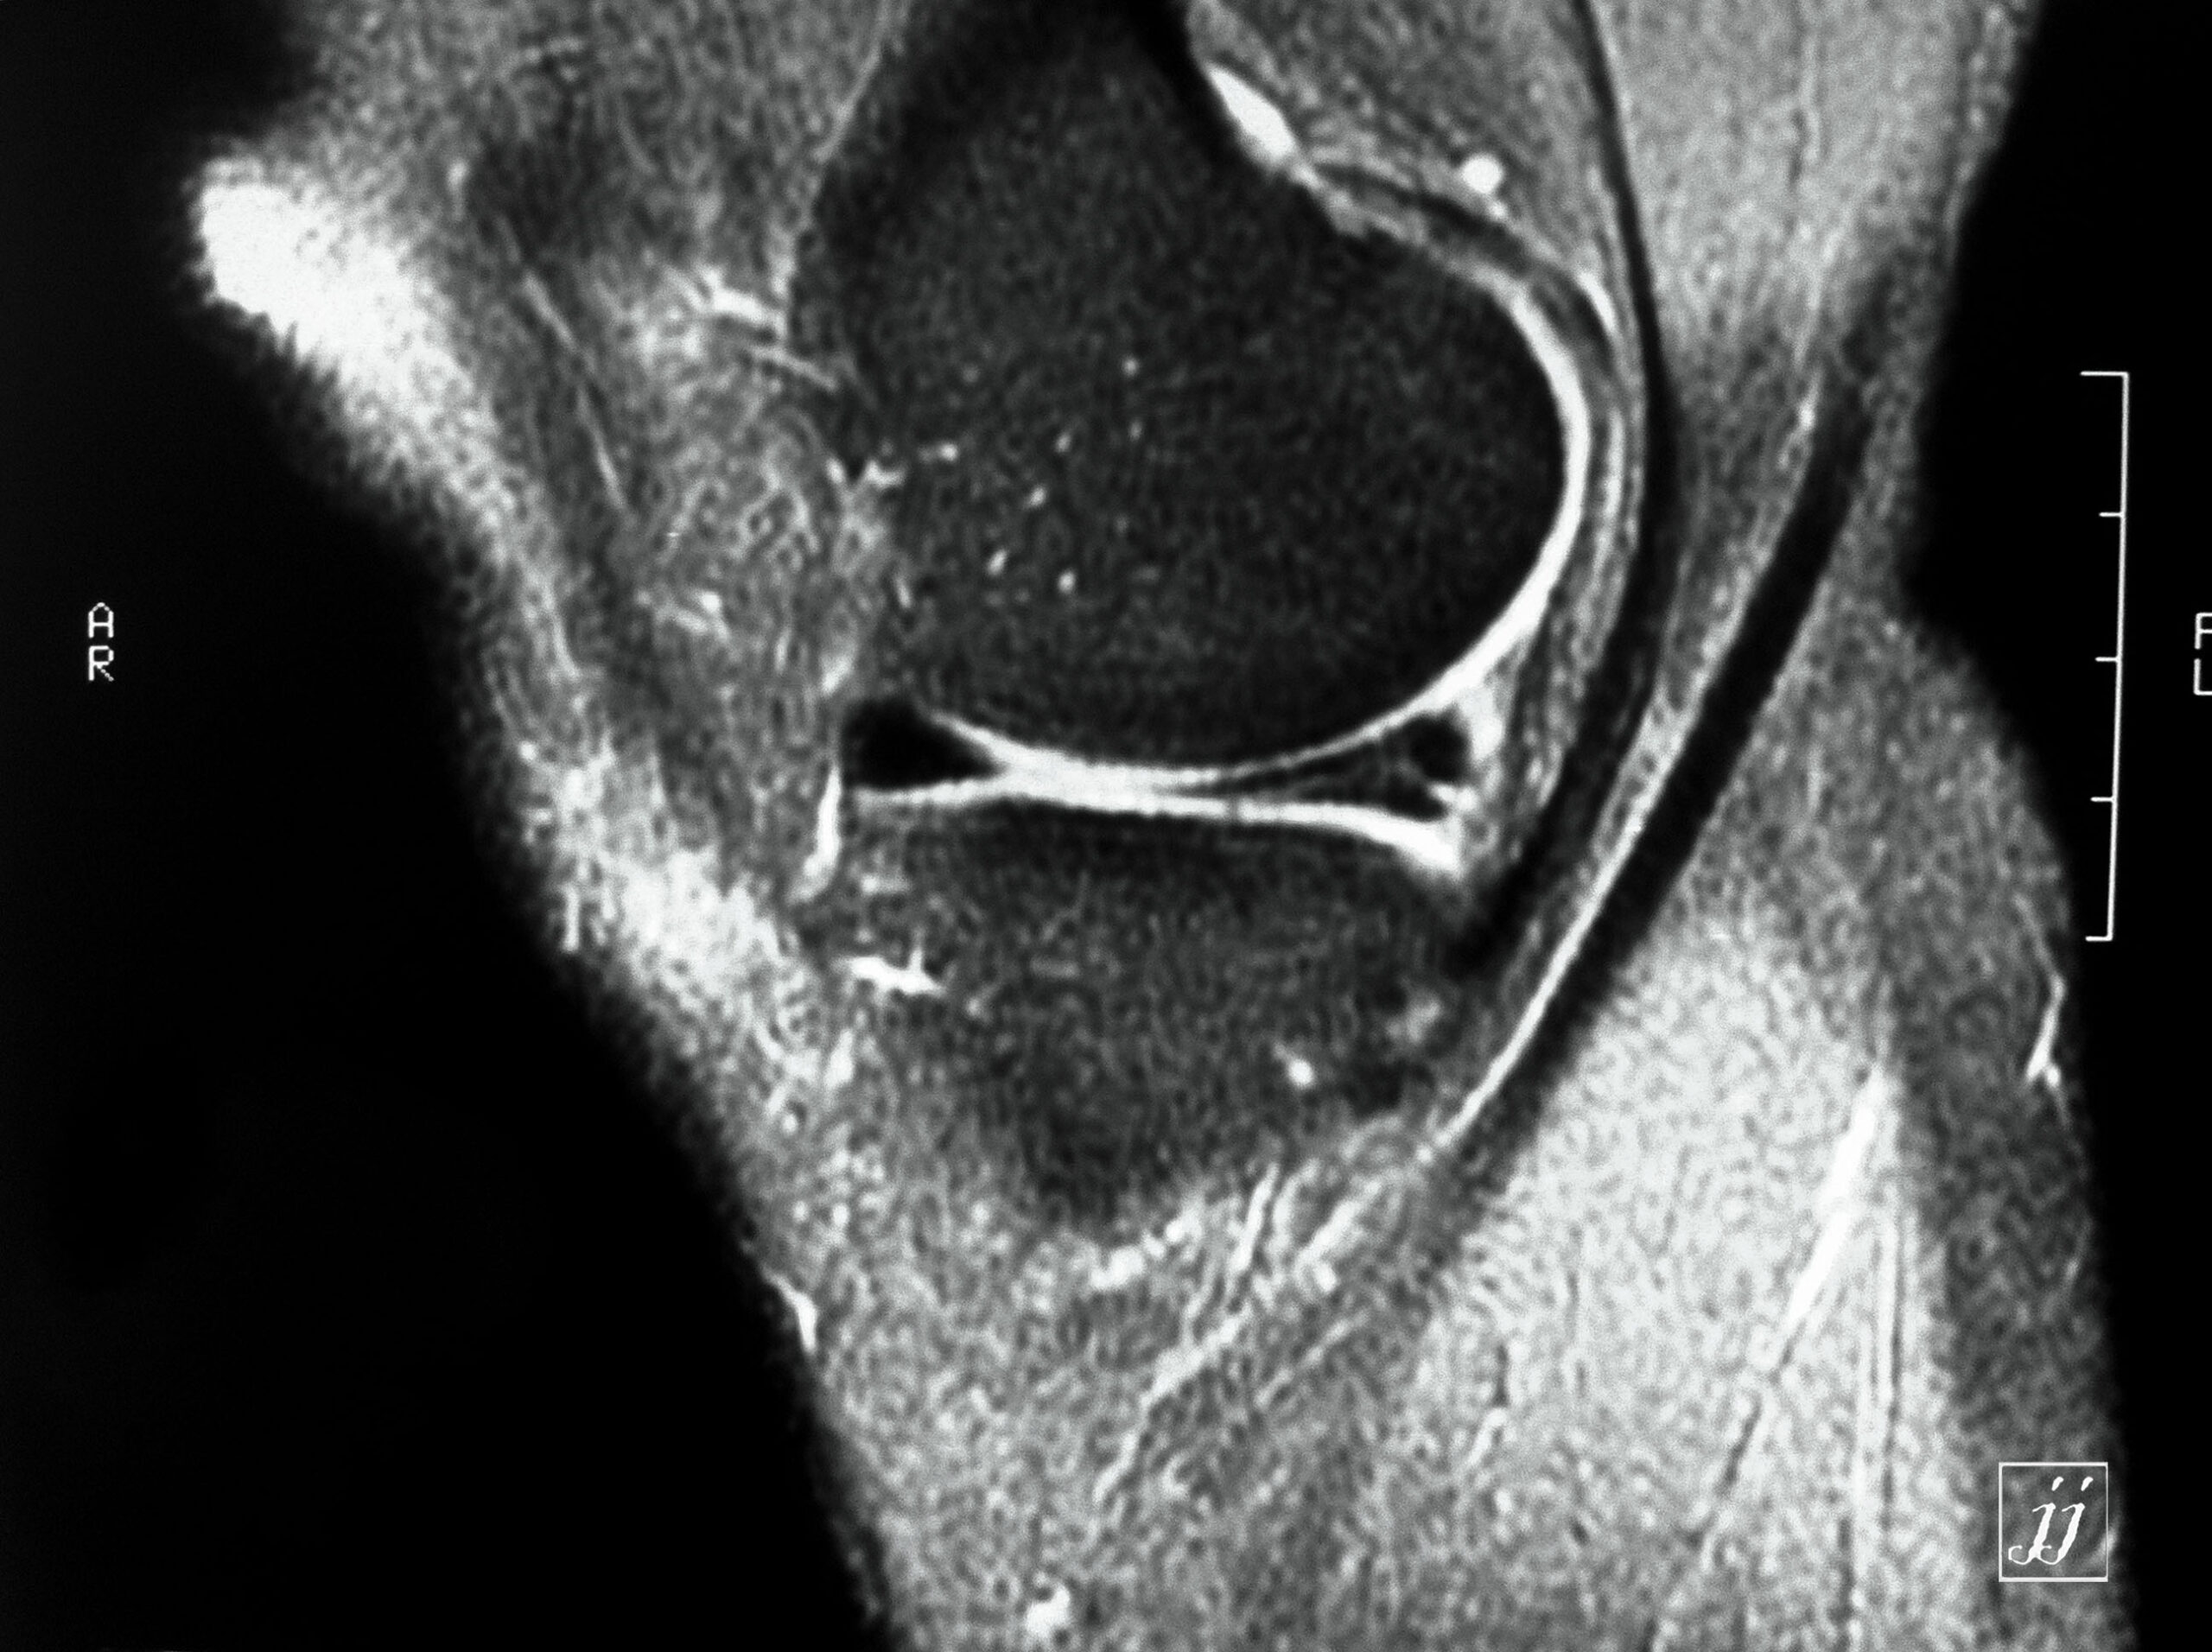

MSK- bi lateral popliteal cyst (8)